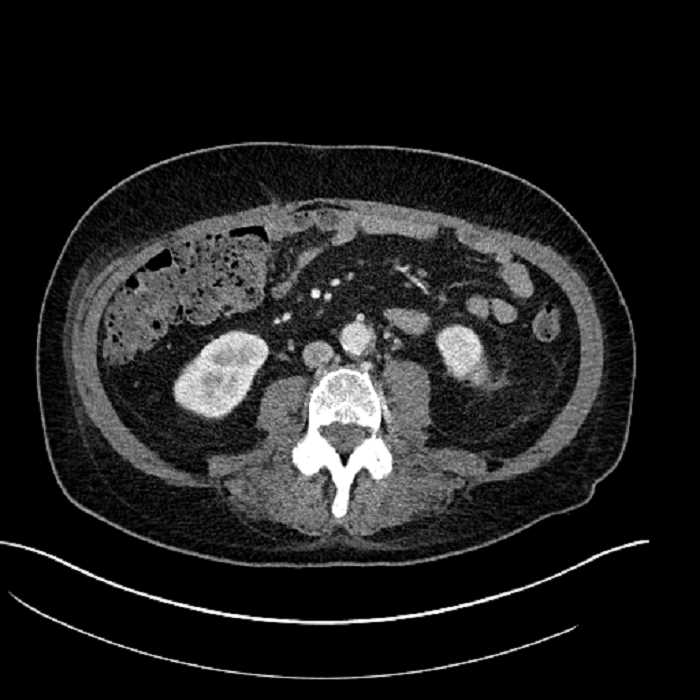

• Large fluid density structure in hepatic segments 7 and 8 measuring 10 x 7 x 7 cm with internal septation and circumferential ill-defined low density compatible with edema

• Peripherally enhancing subcapsular collections along the anterior margin of the left hepatic lobe measuring 3 x 1 cm and 2 x 1 cm

• Clearly marginated fluid density structure in segment 7 and several other scattered tiny hypodensities, which likely represent cysts

• Hepatic abscess

• The classic CT imaging appearance is a double target sign with internal low density surrounded by an internal enhancing rim (capsule) and a low density external rim (edema)

Hepatic abscess showing the double target sign with low density internally surrounded by a thin inner enhancing rim (red arrow) and ill-defined outer low density rim (yellow arrow). Blue arrow indicates an internal septation. Red arrows: additional smaller subcapsular abscesses. Red arrow: focal contained perforation associated with diverticulitis.